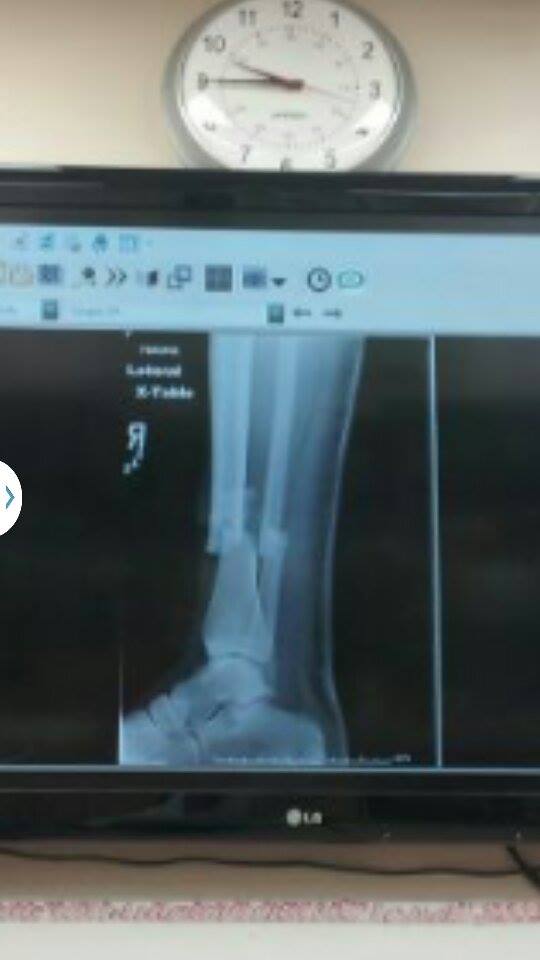

After two years away from the trail, Gregg Hein was ready to reconnect with the backcountry on a solo backpacking trip through Kings Canyon National Park. But when a heavy boulder left three inches of bone sticking out of his leg, his adventure turned into something very different.